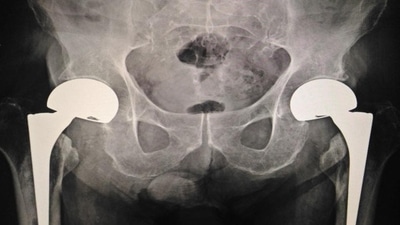

The study was conducted on more than 300,000 Danish people aged 50 or older who had sustained a fracture. In patients with fractures closer to the centre of the body (for example, in the hip, spine, upper arm or leg), the researchers found a higher mortality rate than expected for the general population of the same age. If those people with fractures also had multiple or complex health conditions, the mortality risk was higher again.

Interestingly, a fracture located closer to the centre of the body, like hip, vertebrae or upper arm bones had a higher risk of mortality. By contrast, those in the healthy group who had fractures further away in the body, such as hands and forearms, had virtually no increase in mortality rate.

The presence of specific clusters of health conditions in people compounded the chance of death following these fractures, much greater than either fractures or health conditions alone. For instance, the mortality rate following hip fracture amongst men in the cancer cluster was 41% higher than similarly aged men in the general community. And diabetes in otherwise healthy people was not associated with increased mortality risk, but diabetes in combination with heart, vascular or kidney disease was.